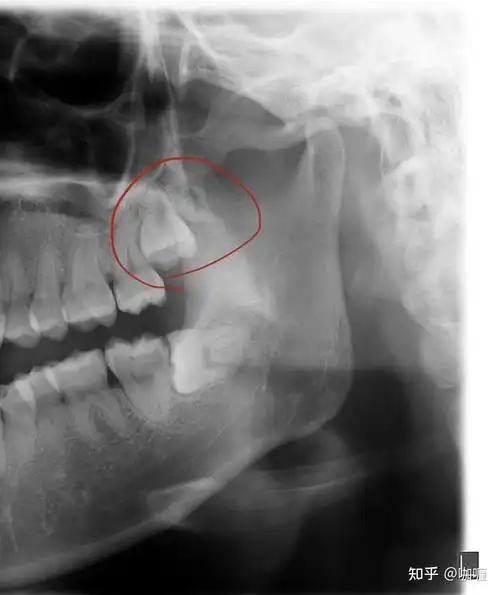

在杭口拔一颗普通智齿 - 知乎